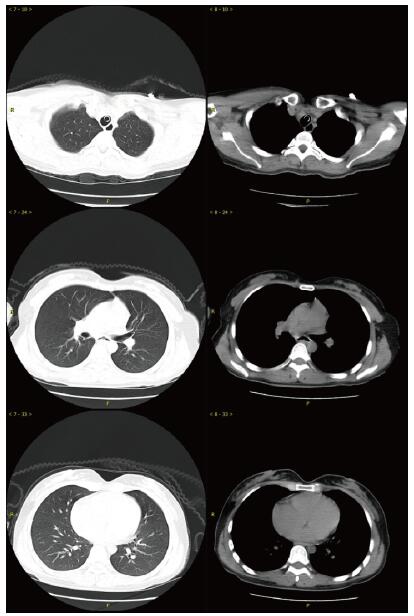

当晚20时到达本院,入院时患者昏迷,血压低、心肌损伤、轻度心衰, 低氧血症, 肝损伤。相关实验室检查:血气PaO2 44 mmHg,生化指标谷丙转氨酶(ALT)528.8 U/L,谷草转氨酶(AST)780.9 U/L,胆红素正常,尿素氮(BUN)3.6 mmol/L,肌酐(Cr)125.7 μmol/L,血糖7.88 mmol/L,心肌肌酐蛋白(cTnT)55.94 ng/mL,N末端B型利钠肽原(NT-pro BNP)495.7 pg/mL,神经元特异性烯醇化酶(NSE)47.46 ng/mL。胸部CT未见明显异常(图 1),头颅CT未见明显异常(图 2A)。给予异甘草酸镁保肝,乙酰半胱氨酸抗氧化,兰索拉唑保护胃黏膜,并予血液灌流治疗一次。

| 图 1 患者入抢救室时肺部CT影像 |

次日晚间收住入院。住院第2天监测血压99/72 mmHg。实验室检查:cTnT 245.4 ng/L,NT-pro BNP 18.57 pg/mL,BUN 2.68 mmol/L,Cr 40.5 μmol/L,血钾3.82 mmol/L。血气:PO2 116 mmHg,pH 7.498, Lac 1.58 mmol/L。并CRRT治疗:治疗前APTT为32.2 s,阿加曲班抗凝,治疗剂量40 mL/(kg·h)。第3天继续CRRT治疗,阿加曲班抗凝,监测APTT为62.9 s(为正常值2倍)。第4天停CRRT, 记录自发尿量1 920 mL /24 h。第5天神志逐步转清,有指令动作,自主呼吸良好,停机械通气。脱机拔管后查颅脑CT双侧基底节区及脑干低密度影, 考虑中毒性脑病改变(图 2B),胸部CT未见明显异常。监测APTT为26.7 s。第7天患者再次昏迷,并有呼吸急促,脉氧下降。再次行气管插管呼吸机支持。监测肝功能进一步好转(ALT 187.7 U/L,AST 92.2 U/L)。第8天17时发现患者瞳孔不等大,左侧3.5 mm,右侧4.5 mm, 对光反射消失,即查颅脑CT示右侧基底节区出血(图 2C)。家属要求保守治疗。第9天患者处于深昏迷状态,家属放弃继续治疗出院。出院一周后随访患者死亡。

哒螨灵口服中毒后机体细胞内呼吸功能抑制,导致细胞缺氧,无糖酵解,乳酸快速堆积,机体迅速出现代谢性酸中毒,重要脏器灌注不足,早期即可表现肝功能异常甚至肝衰竭;心肌酶谱增高,心肌收缩力减低,胰腺功能受损,血淀粉酶增高,血糖应激性增高[3]。由于人体脑组织供应的血流非常丰富,因此对缺氧表现也非常敏感。但哒螨灵中毒并发脑病报道较少,并发脑出血者罕见。该例患者中毒后出现恶心呕吐,提示该药对胃肠道有刺激性;后出现多系统损伤。早期即出现意识障碍,并渐加重至昏迷,有脑神经元损伤,但早期头颅CT未见明显异常;患者有严重低血压,需要大剂量血管活性药物维持血压;患者严重低氧血症,需要呼吸机支持,但肺部影像学未见明显异常;患者有乳酸酸中毒、肝肾功能损伤和心肌受损,但上述损伤大多在支持治疗2~4 d后完全正常或出现明显好转。但第5天头颅CT提示患者出现中毒性脑病表现,患者神志在短暂好转后又再次恶化,第8天原右侧基底节区水肿部位出现脑出血。